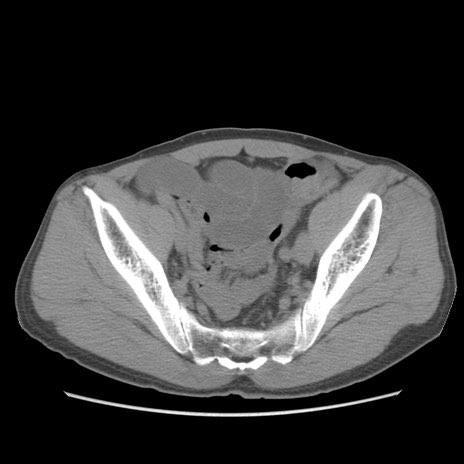

症例56 CT(横断像)

脂肪ウインドウ